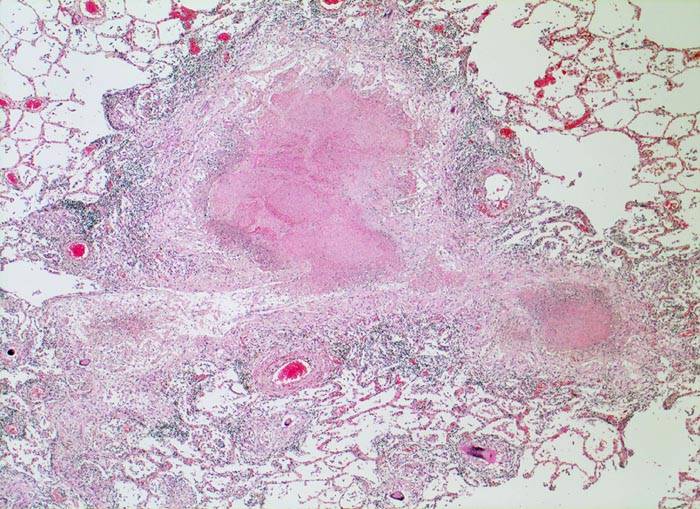

PathoPic – image database / PathoPic ID 4831 - azinös-nodöse Lungentuberkulose

azinös-nodöse Lungentuberkulose

Exsudative Granulome in unmittelbarer Umgebung von Gefässen. Der zugehörige Bronchiolus ist vollständig entzündlich zerstört. Die Granulome bestehen aus einer zentralen käsigen Nekrose umgeben von einem helleren Epitheloidzellwall und ganz aussen einem blauen Saum von Lymphozyten. Daneben einzelne kleinere rein produktive nicht verkäsende Granulome.

Autoptisch wird ein akuter Myokardinfarkt der Vorderwand diagnostiziert. In beiden Lungen fallen oberlappenbetonte knotige weisse, teils kleeblattartige Infiltrate auf und eine subapikal gelegene kleine Kaverne. Einzelne hiläre Lymphknoten der rechten Seite weisen Verkalkungen auf und bilden zusammen mit einem subpleural im Mittellappen gelegenen verkalkten Herd den abgeheilten Primärkomplex. In den käsigen Nekrosen können vereinzelte säurefeste Stäbchen nachgewiesen werden.